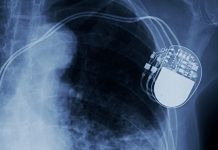

47% of parents experience PTSD after their child’s defibrillator implant

The installation of a cardiovascular defibrillator implant in a paediatric patient is more likely to cause PTSD in the parents of the child than...